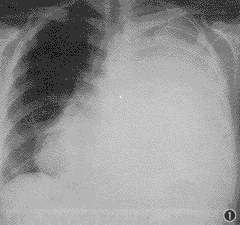

第32例——左胸大片片状阴影一例

患者女性 ......